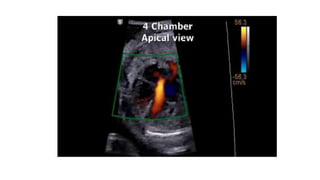

• #16 Heart Position and Axis. Normal position and axis of the heart. The heart is predominantly in the left side of the chest, with the apex of the heart pointing leftward. Dual-screen image shows the stomach also on the left side.